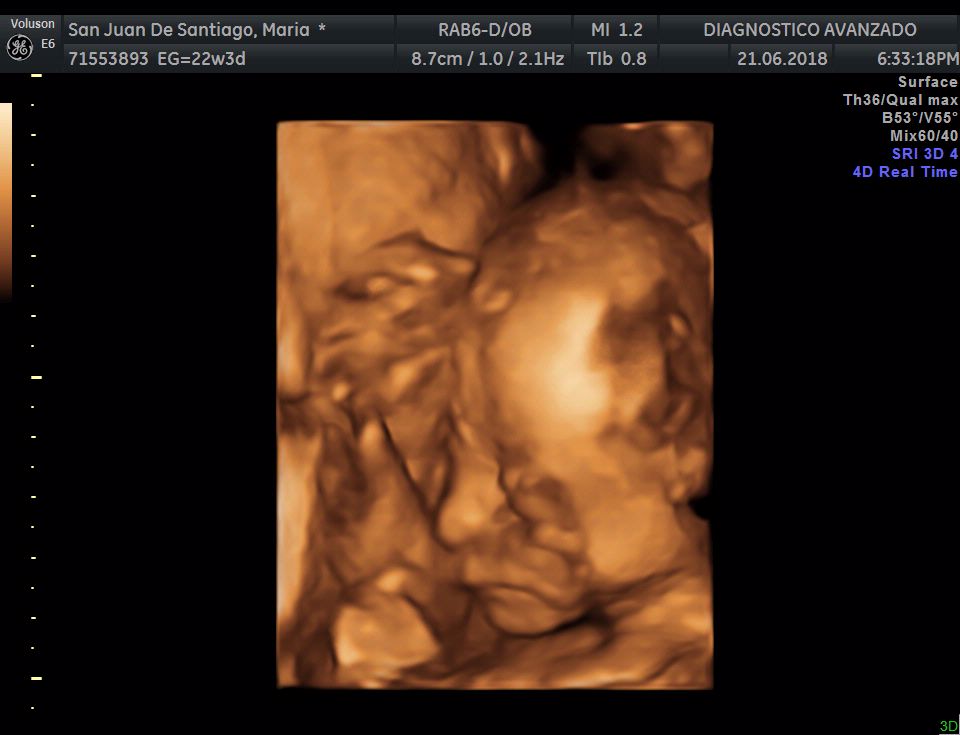

¡Hola a todos! Hoy hemos ido a hacer la tradicional ecografía 3D de la niña, os dejamos todo el material (aunque es un poco demasiado).

Añade el tuyo →Molto felice!!! Commovente!!! Cresce benissimo!